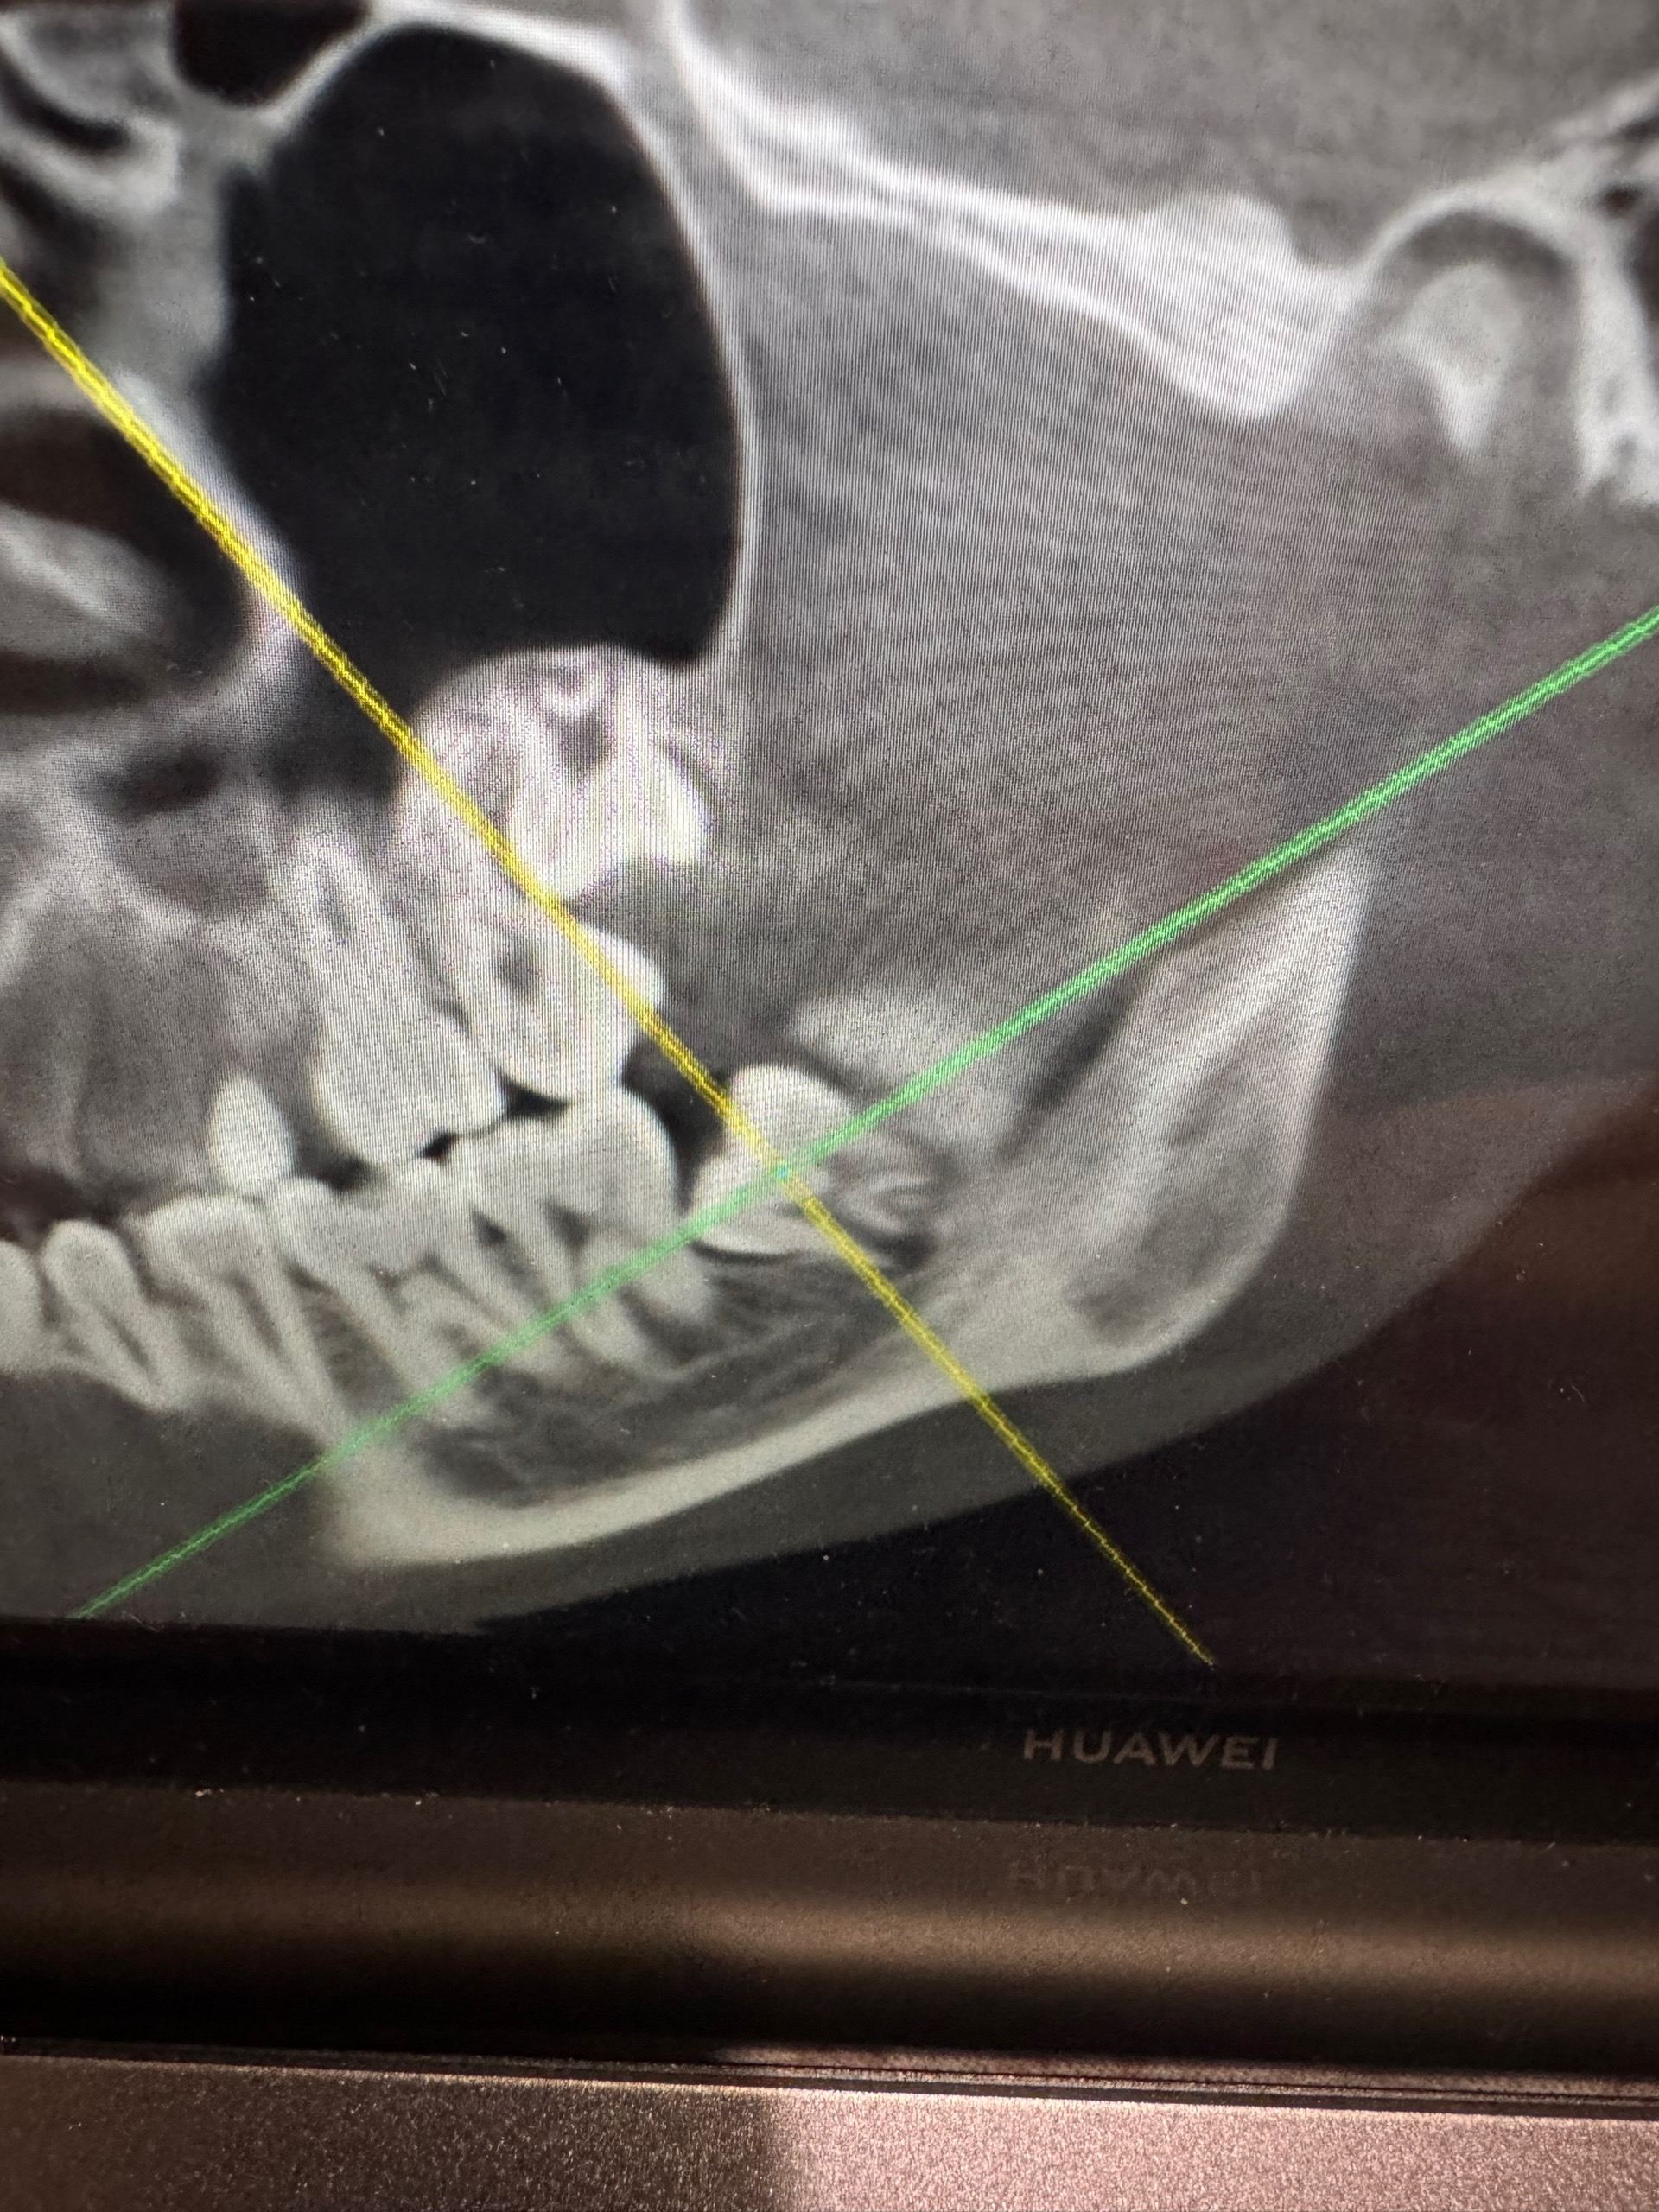

The orthodontist told me I need to have four wisdom teeth removed before getting braces because they're growing in incorrectly and could shift after treatment. I can't refuse, but many people say it reduces bone mass and leads to gum recession (I'm 16, by the way). I've attached a photo.